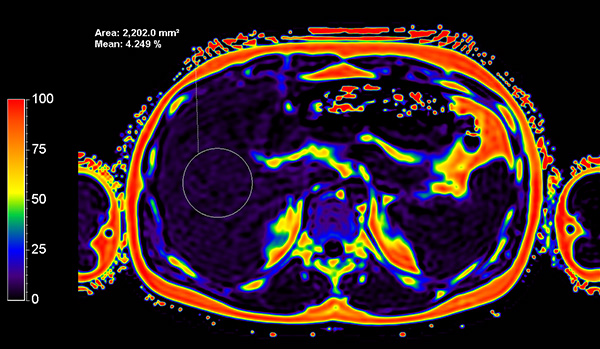

Axial mDIXON Quant (Fat Fraction)